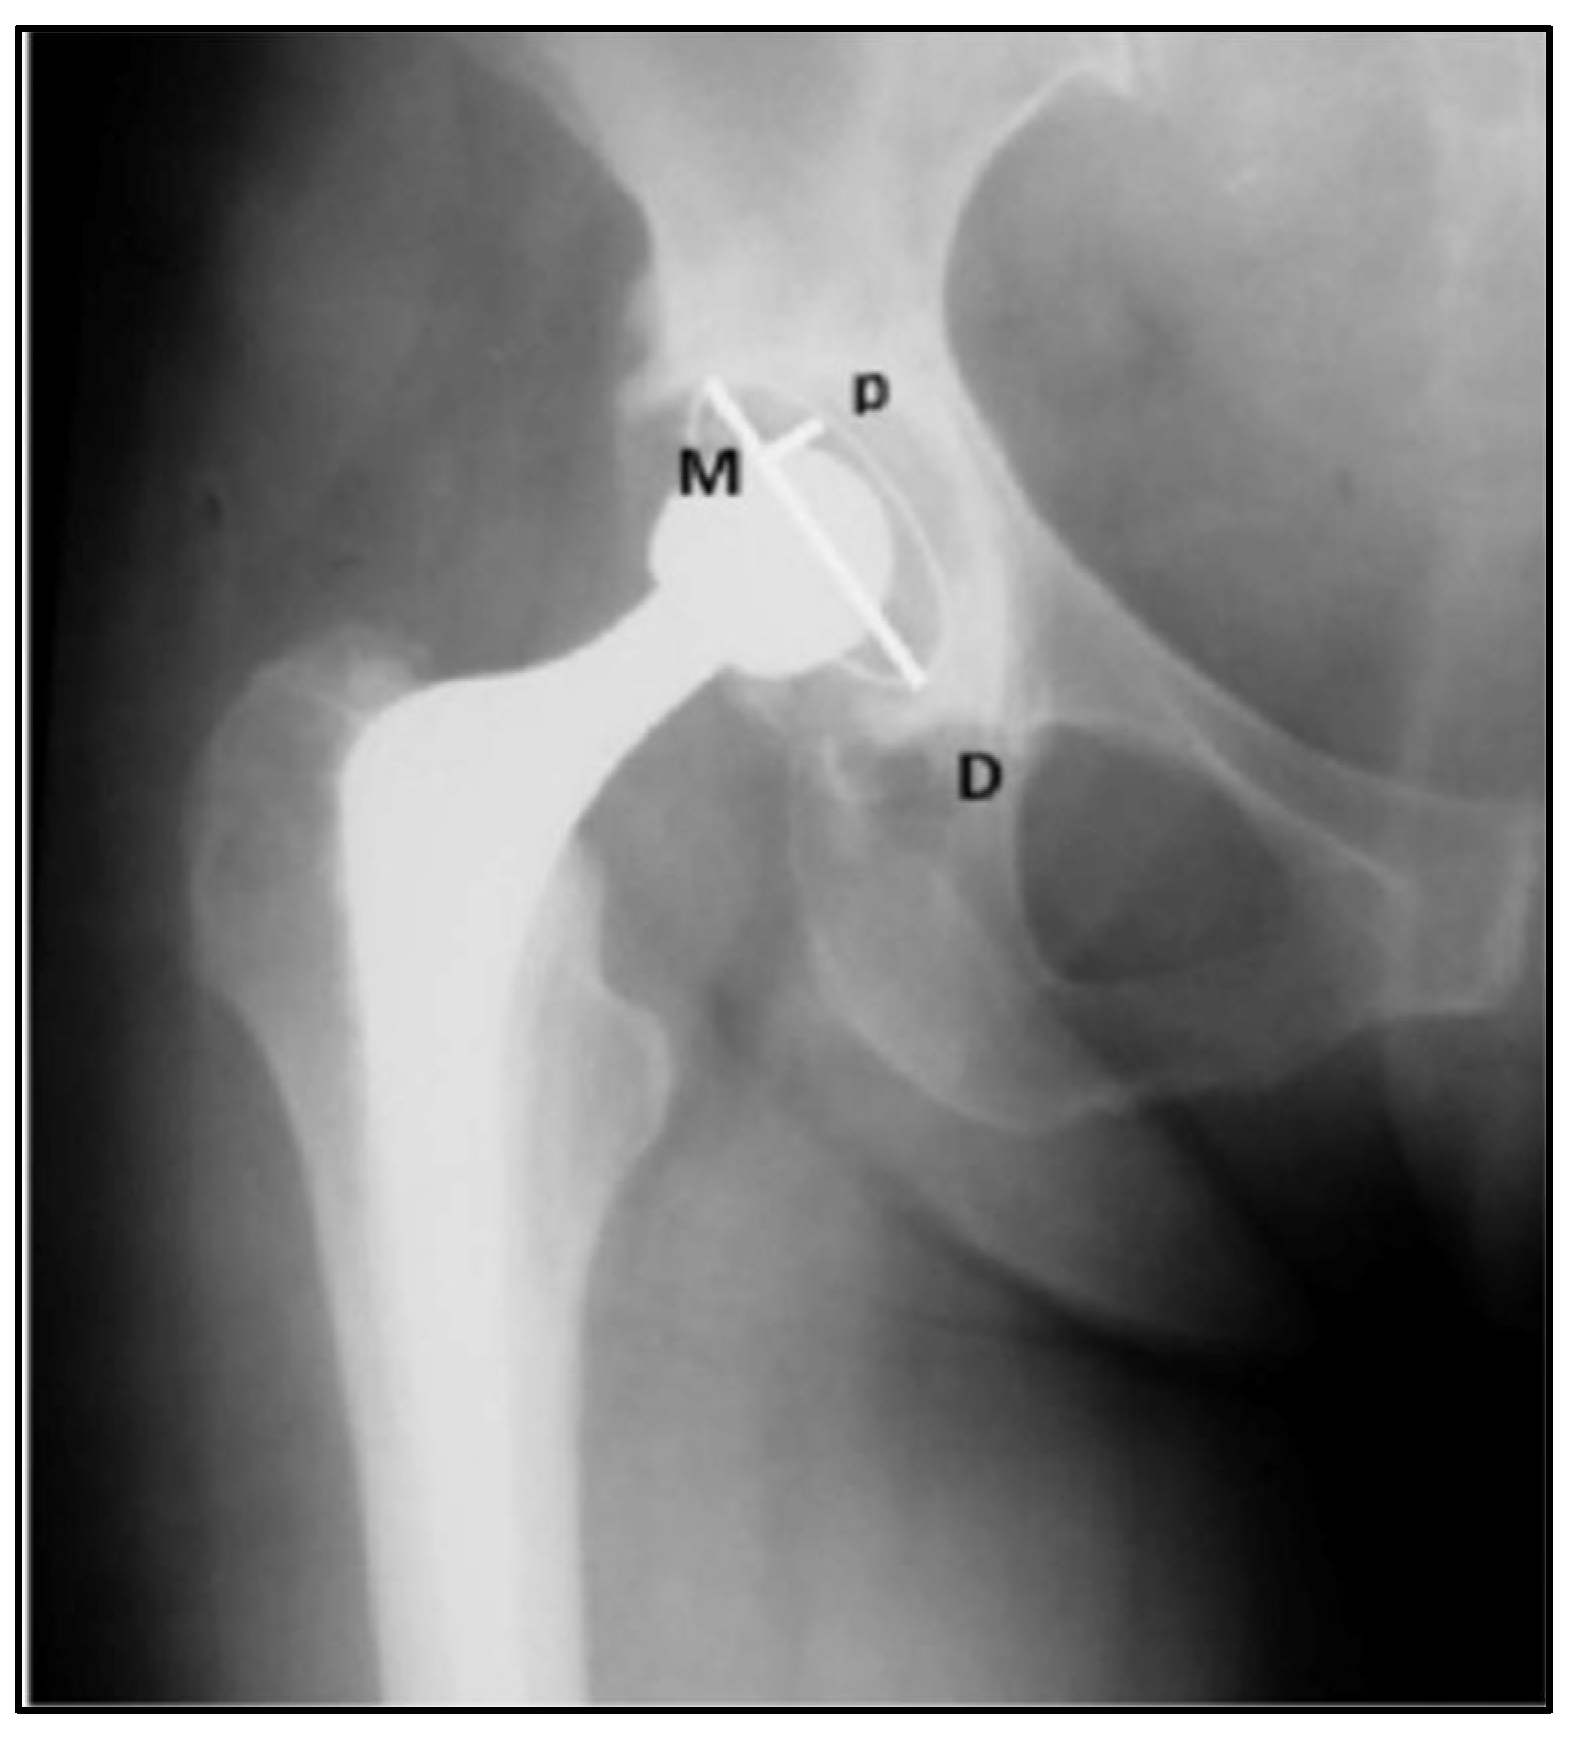

2.3. Analysis of Radiographic Parameters: Positioning and Inclinations of the Acetabular Component